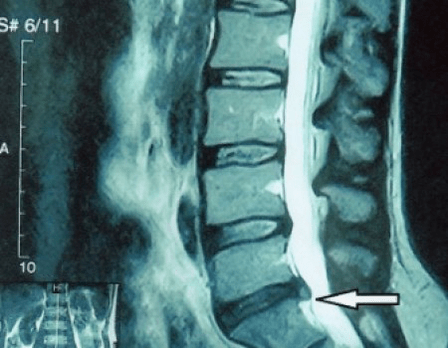

Since the discs themselves can only be seen with CT or MRI, magnetic resonance and X-ray computed tomography are indicated to clarify the internal structure of the cartilage and formations such as protrusions and hernias.Thus, with the help of these methods, an accurate diagnosis is made, and the result of the tomography is an indication and even an up-to-date guide for operative treatment of hernia in the neurosurgery department.

- if you have a hernia, then you need to monitor it dynamically, do regular magnetic resonance imaging, avoid increasing the size or perform modern minimally invasive surgical treatment, since without exception all conservative methods of treatment for exacerbation of osteochondrosis leave the hernia in place and only eliminate temporary symptoms: inflammation, pain, shooting and muscle spasms.

It is desirable that every patient, after progression of symptoms, in the presence of complications, undergo an MRI and consult a neurosurgeon.Modern minimally invasive operations allow safe removal of quite large hernias, without prolonged hospitalization, without having to lie down for several days, without disturbing the quality of life, as they are performed using modern video endoscopic, radio frequency, laser technology or using cold plasma.You can vaporize part of the core and reduce the pressure, reducing the risk of getting a hernia.And you can eliminate the defect radically, that is, by getting rid of it completely.

There is no need to be afraid to operate on hernias;these are no longer the previous types of open surgeries of the 1980s and 1990s with muscle dissection, blood loss and a subsequent long recovery period.They are rather a small puncture under X-ray control, followed by the use of modern technology.